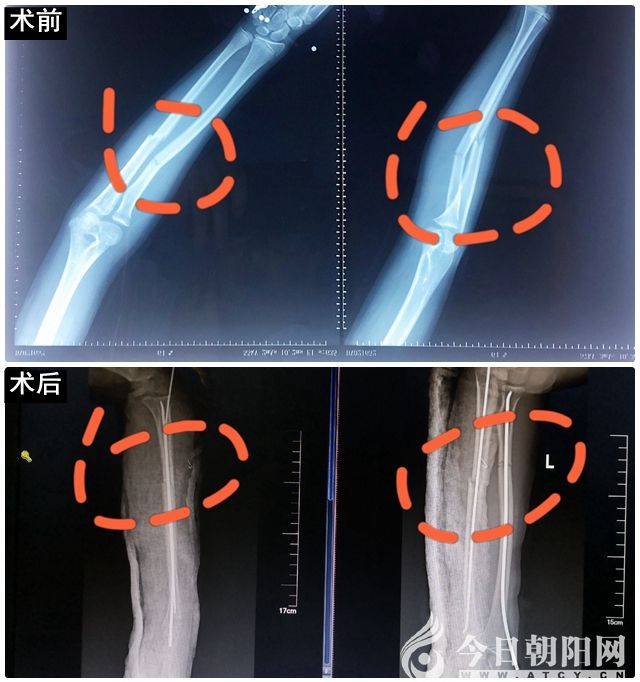

微創(chuàng)先行!市二院成功開展首例兒童尺橈骨骨折閉合復位彈性髓內針固定手術

患兒女性,9歲,因車禍受傷致左前臂尺橈骨骨折,骨折為不穩(wěn)定骨折,移位明顯,非手術不能滿意復位。為了使手術給孩子造成的副損傷降到最低,創(chuàng)傷骨科副主任、主任醫(yī)師李榮華帶領副主任醫(yī)師唐磊、主治醫(yī)師王海軍在術中C臂X光機透視下為患兒實施了骨折閉合復位彈性髓內針固定手術,手術過程順利。參與手術的醫(yī)生術后無私地說:“為了孩子得到最好的治療,多受一些X線輻射也值了。”